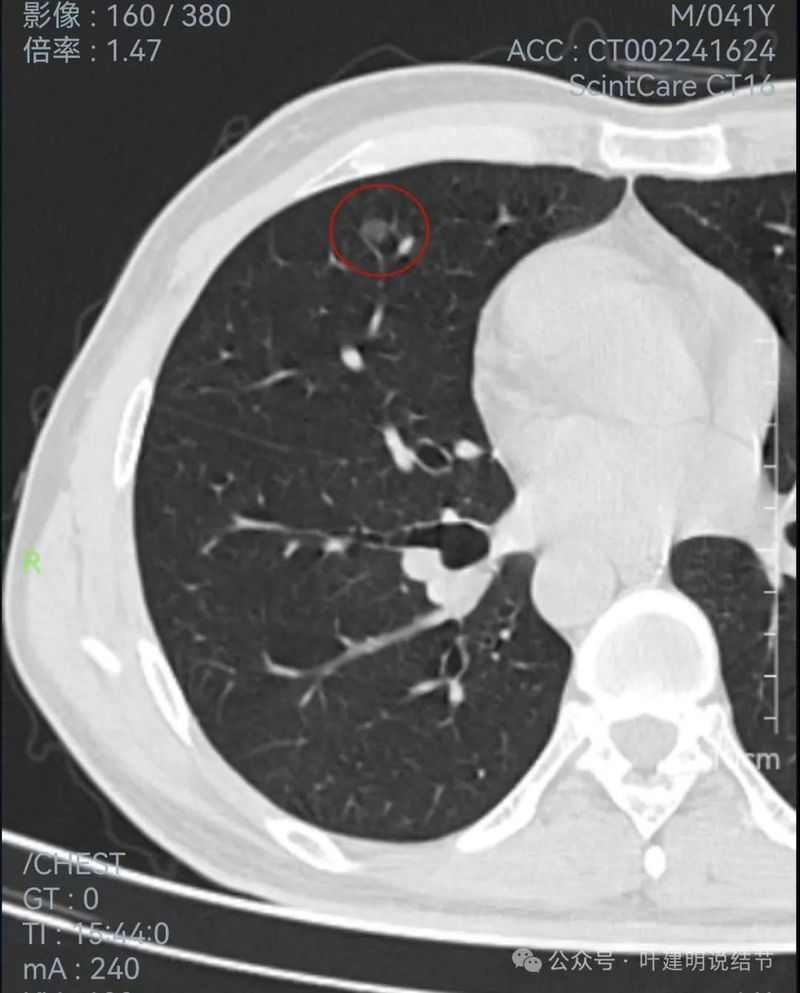

左侧病灶连续层面:

2024年1月靶重建:

密度太高,而且偏长条状。

边缘区密度高,条状。

实性部分密度过高,磨玻璃部分密度淡且瘤肺边界不太清。